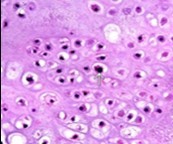

Distinction between benign cartilaginous lesions and atypical cartilaginous tumour or grade 1chondrosarcoma (ACT/CS1) can be challenging, Typically, benign cartilaginous lesions are hypo-cellular, in contrast to hyper-cellular atypical cartilaginous tumour or grade 1 chondrosarcoma 5, 6. Figure 1, Figure 2, Figure 3, Figure 4, Figure 5, Figure 6, Figure 7, Figure 8.

Figure 6.Enchondroma exemplifying lobules of hyaline cartilage composed of enlarged, vacuolated cells with uniform nuclei. Focal calcification is absent 14

Figure 7.Enchondroma enunciating lobular hyaline cartilage with constituent vacuolated chondrocytes an uniform nuclei 15.